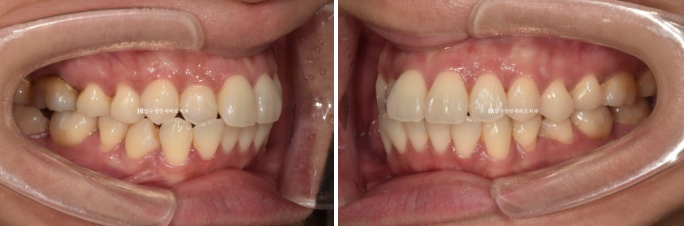

The molar occlusion is in fairly good condition.

First, the patient’s request was, “I want at least the front teeth to be aligned during the 3–4 months before I leave the country.”

There are rotations and level differences in the premolars, but they are not functionally problematic, and the oral hygiene condition is not bad, so we decided to address those issues later with full orthodontic treatment when circumstances allow.

After 4 months of treatment, we finally completed treatment in January 2024.

Left - Before treatment / Right - After treatment

The originally good occlusion was well maintained.